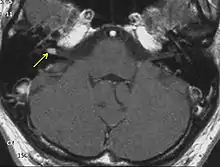

NF2 is a genetically transmitted condition. Diagnosis is most common in early adulthood (20–30 years); however, it can be diagnosed earlier. NF2 can be diagnosed due to the presence of a bilateral vestibular schwannoma, or an acoustic neuroma, which causes a hearing loss that may begin unilaterally.[14] If a patient does not meet this criterion of diagnosis, they must have a family history of NF2, and present with a unilateral vestibular schwannoma and other associated tumors (cranial meningioma, cranial nerve schwannoma, spinal meningioma, spinal ependymomas, peripheral nerve tumor, spinal schwannoma, subcutaneous tumor, skin plaque). This being said, more than half of all patients diagnosed with NF2 do not have a family history of the condition.[14] Although it has yet to be included into clinical classification, peripheral neuropathy, or damage to the peripheral nerves, which often causes weakness, numbness and pain in the hands and feet, may also lead to a diagnosis of NF2. In children, NF2 can present with similar symptoms, but generally causes "visual disturbances (cataracts, hamartomas), skin tumors, mononeuropathhy (facial paresis, drop foot), symptomatic spinal cord tumors, or non-vestibular intracranial tumors".[14]

Bilateral vestibular schwannomas are diagnostic of NF2.[15]